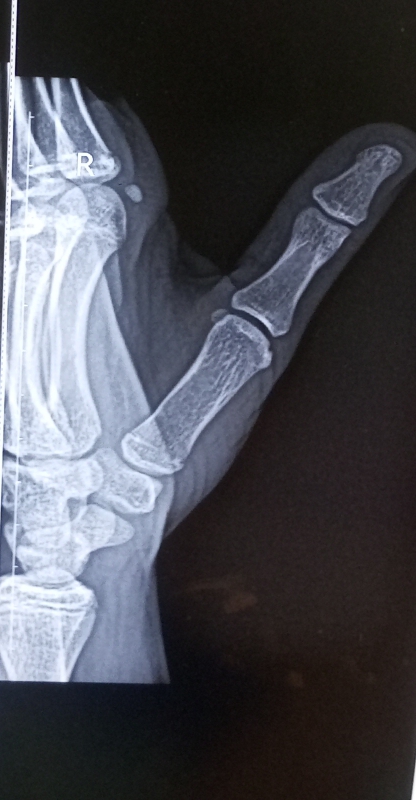

Все ли нормально с большим пальцем на руке?   1 ответ

Полгода назад был сломан большой палец. В среду после небольшого удара он сильно опух и появился большой синяк, при движении сильно болит. Снимки свежие.